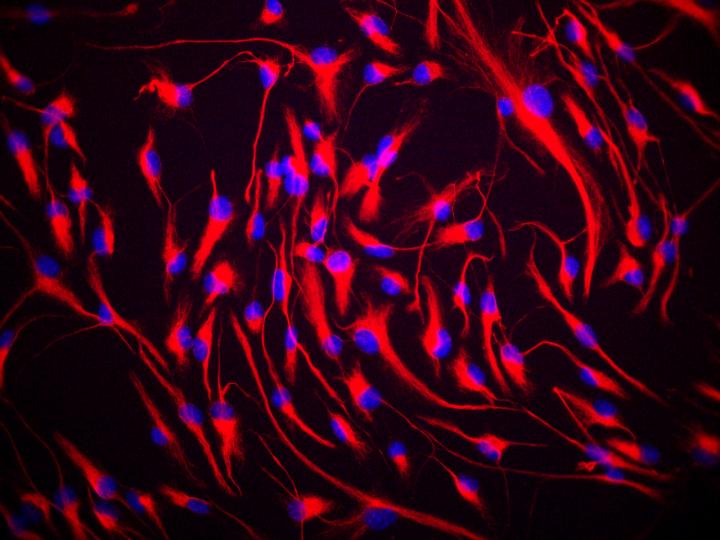

Immagine: cellule staminali del cervello etichettate usando una sostanza che rileva una proteina chiamata nestina che si trova nelle cellule staminali neurali. Credit: Dott. Giuseppe Lupo